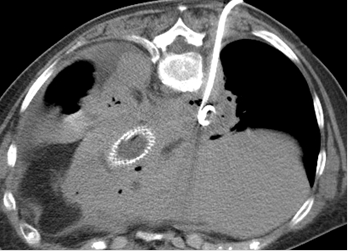

Cas 2 : Pseudo-anévrysme sur branche sous-segmentaire de l’artère pulmonaire droite

après multiples drainages pour infection pleuro-pulmonaire sévère. Contrôle avant et après

embolisation par coil.